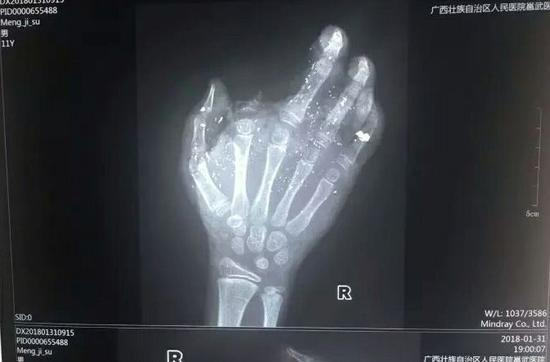

邕武医院急诊科兰天兵医生介绍,孩子送来时伤势很重。右手食指被炸没了,拇指、中指、无名指也都炸伤,失去了供血,手掌皮肤被炸得稀烂。经CT检查,右眼内有2块手机碎片。

记者从医院了解到,孩子断的那根手指已经植不回去了。目前手术通过血管移植,让孩子损伤的另外3个手指恢复了血供,预计今后不会对功能造成太大影响。